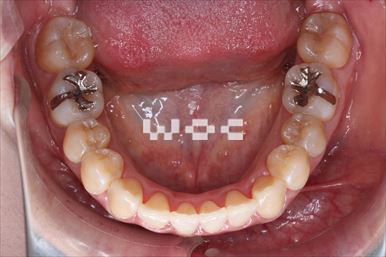

治療中1

治療中2

出っ歯舌側矯正

上下舌側矯正を希望。

通院状況や歯みがきの協力が良かったため、1年7ヶ月で治療を終えることができました。※装置と注意事項に関しては、大人の矯正装置一覧へ。

- 年齢:20歳女性

- 主訴:出っ歯が気になる

- 基本矯正料金:120万円

- 治療期間:1年7ヶ月

- 抜歯部位:上顎両側第一小臼歯